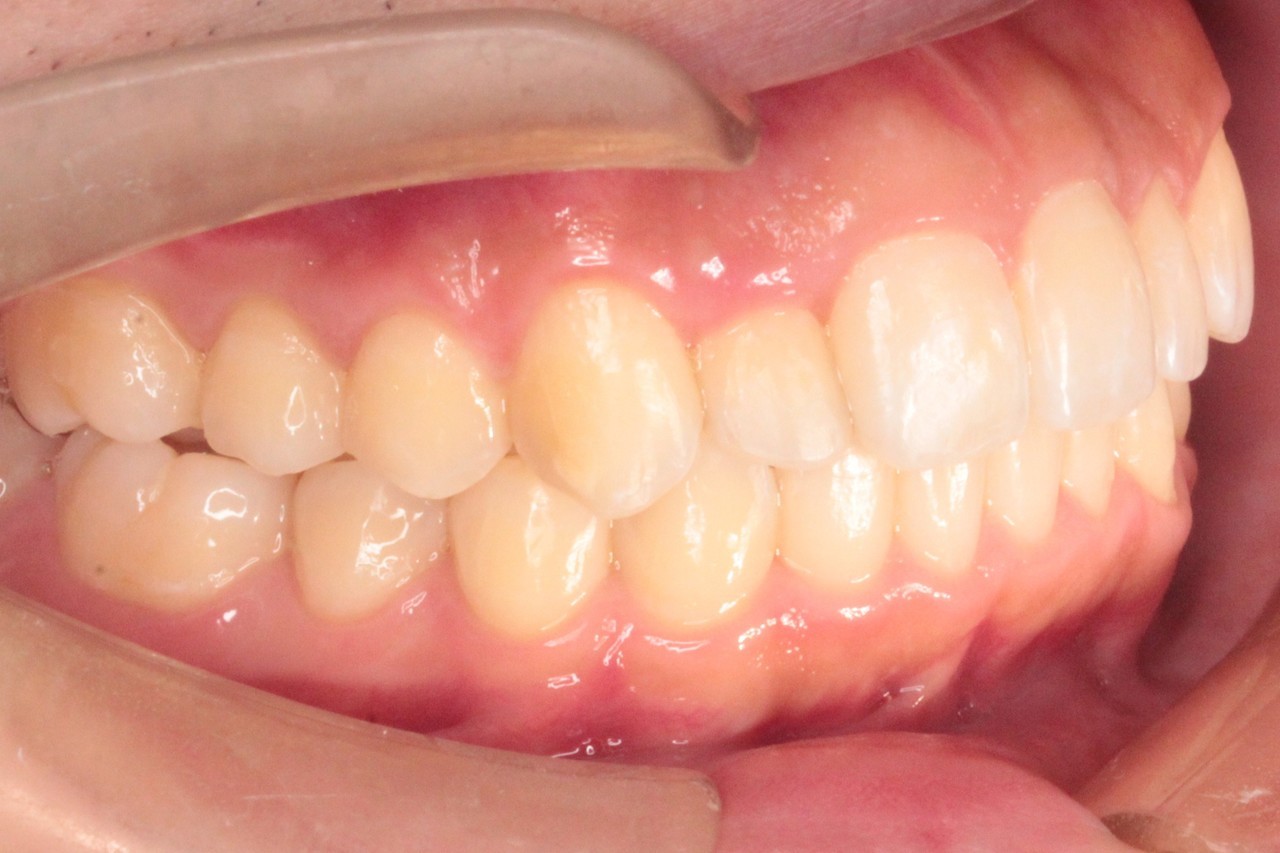

治療後

治療結果:交叉咬合と叢生が改善されました

交叉咬合と重度叢生を非抜歯のインビザラインで治療しました

今回は理想の位置よりもわずかに中に入った位置で矯正終了となることを

事前に患者さまにご了承いただいてからスタートしております